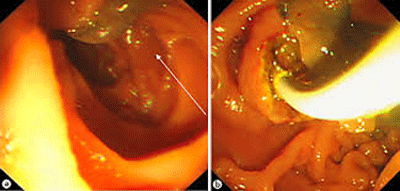

Elizondo (2005) báo cáo ca bệnh viêm tụy cấp ở một bệnh nhân nữ 31 tuổi có bệnh SLGL mạn tính. Nhóm tác giả cho thấy nhiễm trùng như thế làm cho viêm và viêm tụy lan tỏa, phù lớn nhu môvà kết luận viêm tụy là một biến chứng cực hiếm của bệnh SLGL ở hệ gan mật nhưng phải thầy thuốc cần quan tâm đến cơ quan lân cận vì nếu vỡ tụy hoặc xuất huyết-xuát tiết các enzyme từ tụy do sán gây biến chứng sẽ dẫn đến phá hủy các mô, làm nhiễm trùng lan rộng hơn. Việc can thiệp thủ thuật nội soi mật tụy ngược dòng hoặc phẩu thuật hở loại bỏ sán cùng với điều trị nội kho bằng triclabendazole là cách điều trị lựa chọn.

Huỳnh Hồng Quang (2010) cũng đã báo cáo một bệnh nhân nam 42 tuổi tại Quảng Nam nhiễm Fasciola sp. lạc chỗ gây xuyên thủng đường mật, xuất huyết rỉ rả và cần can thiệp nội soi mật tụy ngược dòng, gắp sán ra kết hợp với điều trị nội bằng triclabendazole, nhưng không cầm máu hẳn nên bác sĩ phải mổ hở để giải quyết. Chụp MRI sau 3 tháng điều trị không còn thấy vệt sán cũng như chít hẹp hoặc các thương tổn nhu mô gan mới do sán Fasciola sp. gây ra.